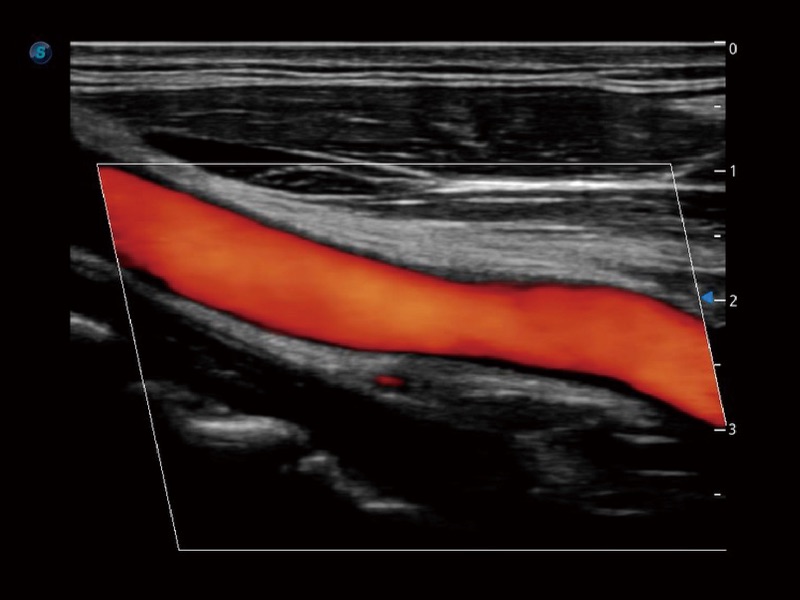

血管内中膜的厚度值是预测心血管疾病风险的重要指标,Auto IMT可以实现血管近场和远场内中膜厚度的自动测量,为临床提供快捷有效的诊断工具。

心血管应用